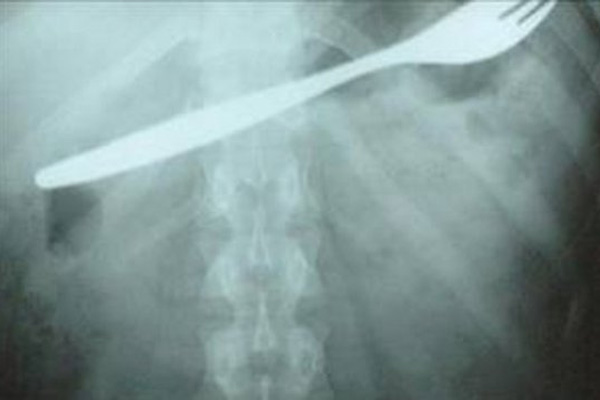

Midesinden çatal çıktı!

Konya'da bir gencin yuttuğu 15 santimetrelik metal çatal, ameliyatla midesinden çıkarıldı.